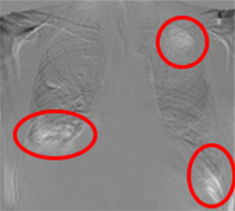

注意:赤枠は実際には表示されません。

◆変化が可視化され、新規病変の認識がしやすくなる。

◆肺門部や心臓裏の見落としやすい部位の病変が見つけやすくなる。

経時変化の差がドーナツ形状として現れることで、一見「変化なし」としがちな病変の大きさ変化が認識可能です。

肺門部裏は見落としやすく重要な読影ポイントですが、経時差分画像により一目で変化が確認出来ます。

左肺尖部に濃度の上昇がありますが、通常画像では淡い変化の為、直ぐに気づきません。読影が難しい肺尖部の鎖骨裏などでも経時差分画像で即座に変化を確認できます。

定期健康診断で検出された症例です。経時差分画像により、肺野外の病変異常に対しても変化を把握し易くなります。